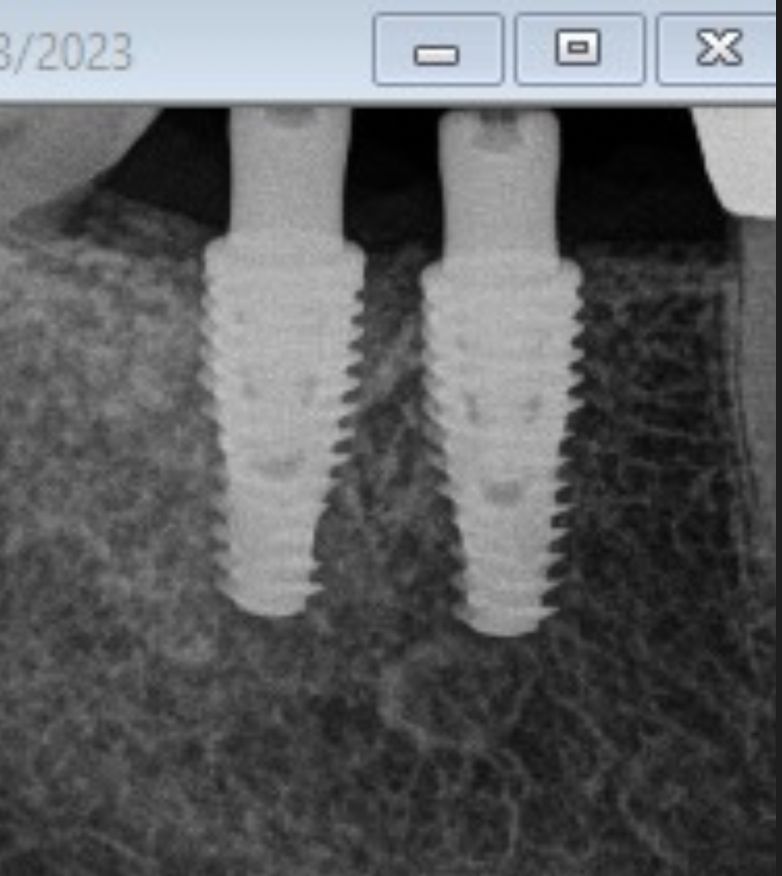

Los implantes dentales son la forma mas estética y funcional de sustituir una diente perdido, ya sea por caries, enfermedad periodontal, traumatismo o agenesia. Lo mas importante para que este tratamiento sea exitoso es su correcta planeación.